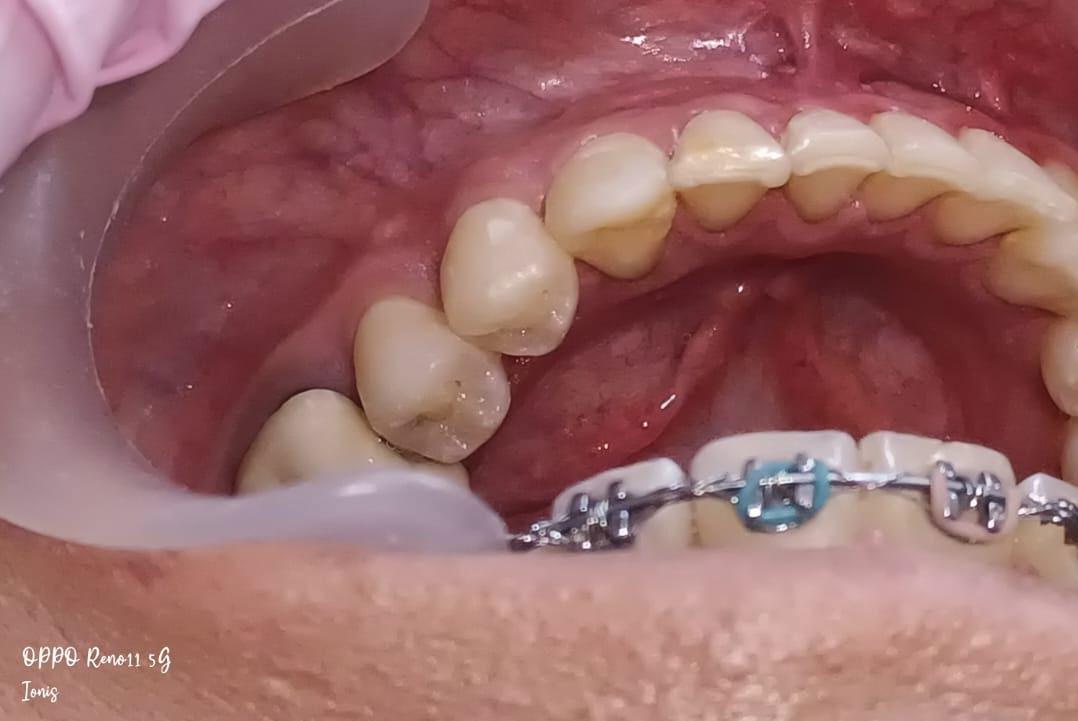

En los estudios intraorales, las fotografías iniciales muestran clase I canina y molar bilateral, mordida anterior abierta, apiñamiento leve superior e inferior, y líneas medias dentales

desviadas. En las Figuras 4, 5 y 6 se observa la forma de las arcadas superior e inferior.

Figura 4. Lateral derecha.

Figura 5. Intraoral de frente e izquierda.